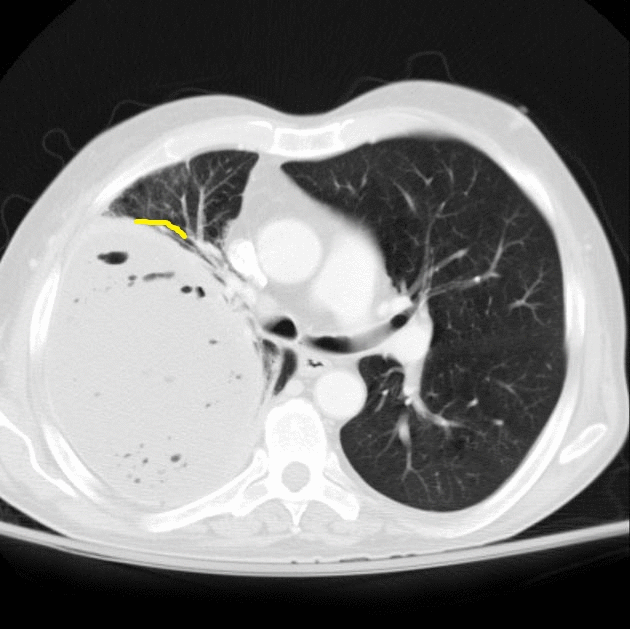

Pleural tags on CT Type 1 (A, F), Type 2 (B), Type 3 (C), Type 4 (D Pleural Tag Sign Radiology By univariate analysis and multivariable adjustment, surgical history, tumour marker (tm), number of pleural tags, length of solid contact and obstructive inflammation were identified as independent risk predictors of pleural invasiveness (p= 0.014, 0.003, <0.001, <0.001, and 0.017, respectively). Department of radiology, concord repatriation general hospital, concord, new south wales, australia. Juxtapleural lung nodules can be defined by their location. Pleural Tag Sign Radiology.

Pleural tags on CT Type 1 (A, F), Type 2 (B), Type 3 (C), Type 4 (D Pleural Tag Sign Radiology Department of radiology, concord repatriation general hospital, concord, new south wales, australia. Intrapulmonary lymph nodes are typically. Pleural tags refer to slender bridges of soft tissue seen on ct scans that extend between masses in the lungs and the pleura. Juxtapleural lung nodules can be defined by their location within 15 mm of a pleural surface. Type 2 pleural tags. Pleural Tag Sign Radiology.

CT images depicting pleural contact with ISP in lung window settings Pleural Tag Sign Radiology Department of radiology, concord repatriation general hospital, concord, new south wales, australia. Intrapulmonary lymph nodes are typically. Juxtapleural lung nodules can be defined by their location within 15 mm of a pleural surface. Type 2 pleural tags on conventional ct images can increase the accuracy of early diagnosis of visceral pleural invasion by nsclc that does not abut the. By. Pleural Tag Sign Radiology.